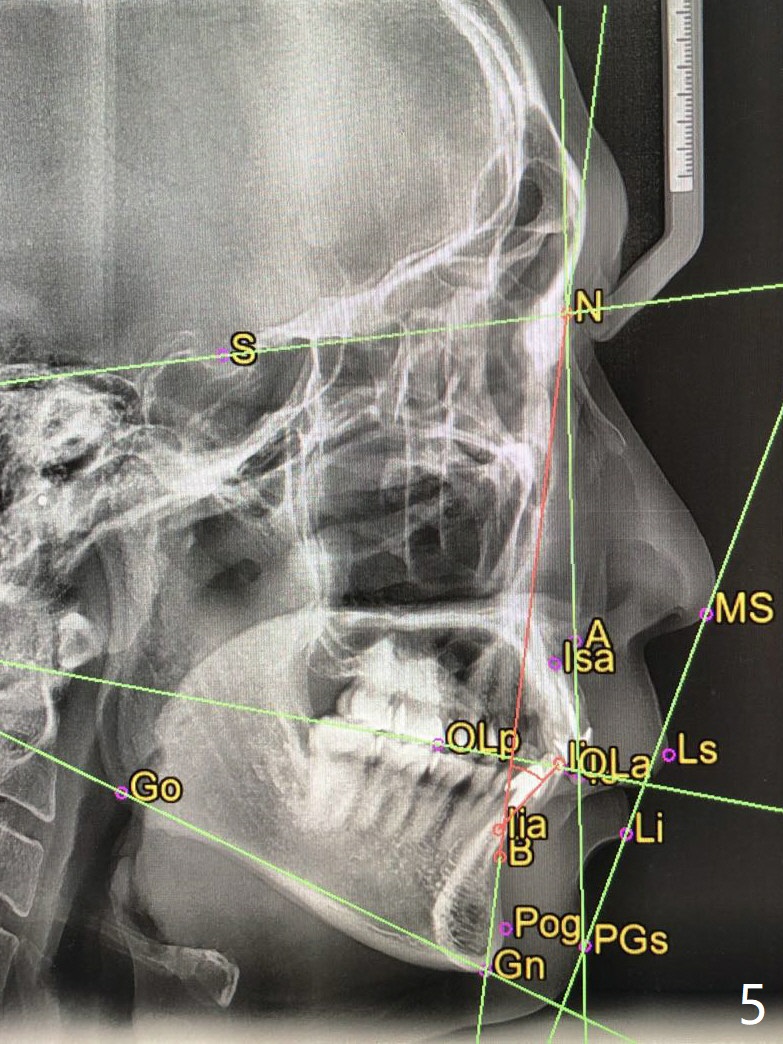

42岁男,小的时候做过矫正,据说智齿萌出后,畸形复发(图一至三)。临床检查显示:上前牙前突,下门牙拥挤,磨牙二类咬合。头颅侧位定位片证明Class II Division I Malocclusion (图四至六):SNA 84.63, SNB 76.11, ANB 8.52。 下周病人复诊,将拍摄照片,取模。正在考虑是否需要拍摄CT,排除上,下切牙是否位于牙槽骨唇侧,有利于做出拔牙决定。